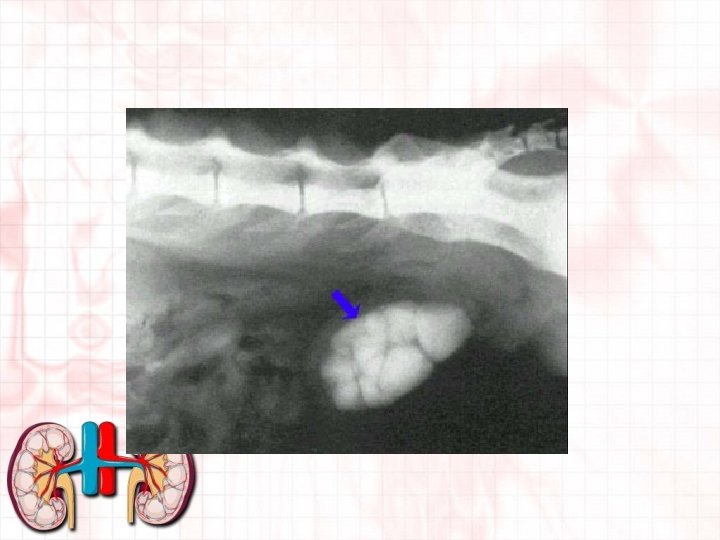

Uroliths and Urolithiasis • Uroliths- aggregates of crystals in the urine that may become urolithiasis. • Urolithiasis- the presence of urinary stones in the bladder. • Usually are formed when the p. H of the urine is too low or too high. • Bacterial infections or diet may influence the p. H levels. • May have a mixed stone.

Struvite stones and crystals • Usually formed when the p. H of the urine is too high. • Sometimes called Triple phosphate or magnesium ammonium phosphate hexahydrate. • 85% of patients with struvite bladder stones are female • Breeds felt to have an increased risk for the formation of struvite stones are the Beagle, Miniature Schnauzer, and English Cocker Spaniel • Generally can be large and smooth in appearance.

Calcium oxalate crystals and stones • Generally formed when the p. H of the urine is too low. • More prevalent in males than females. • Breeds at especially high risk include: Miniature schnauzers, Lhasa Apsos, Yorkshire Terriers, Miniature Poodles, Shih Tzus, and Bichon Frises. • Bichon’s tend to start to form new stones immediately after old stones are surgically removed. • Less likely to be affected by diet and so surgical removal is sometimes necessary. • Usually rougher in appearance